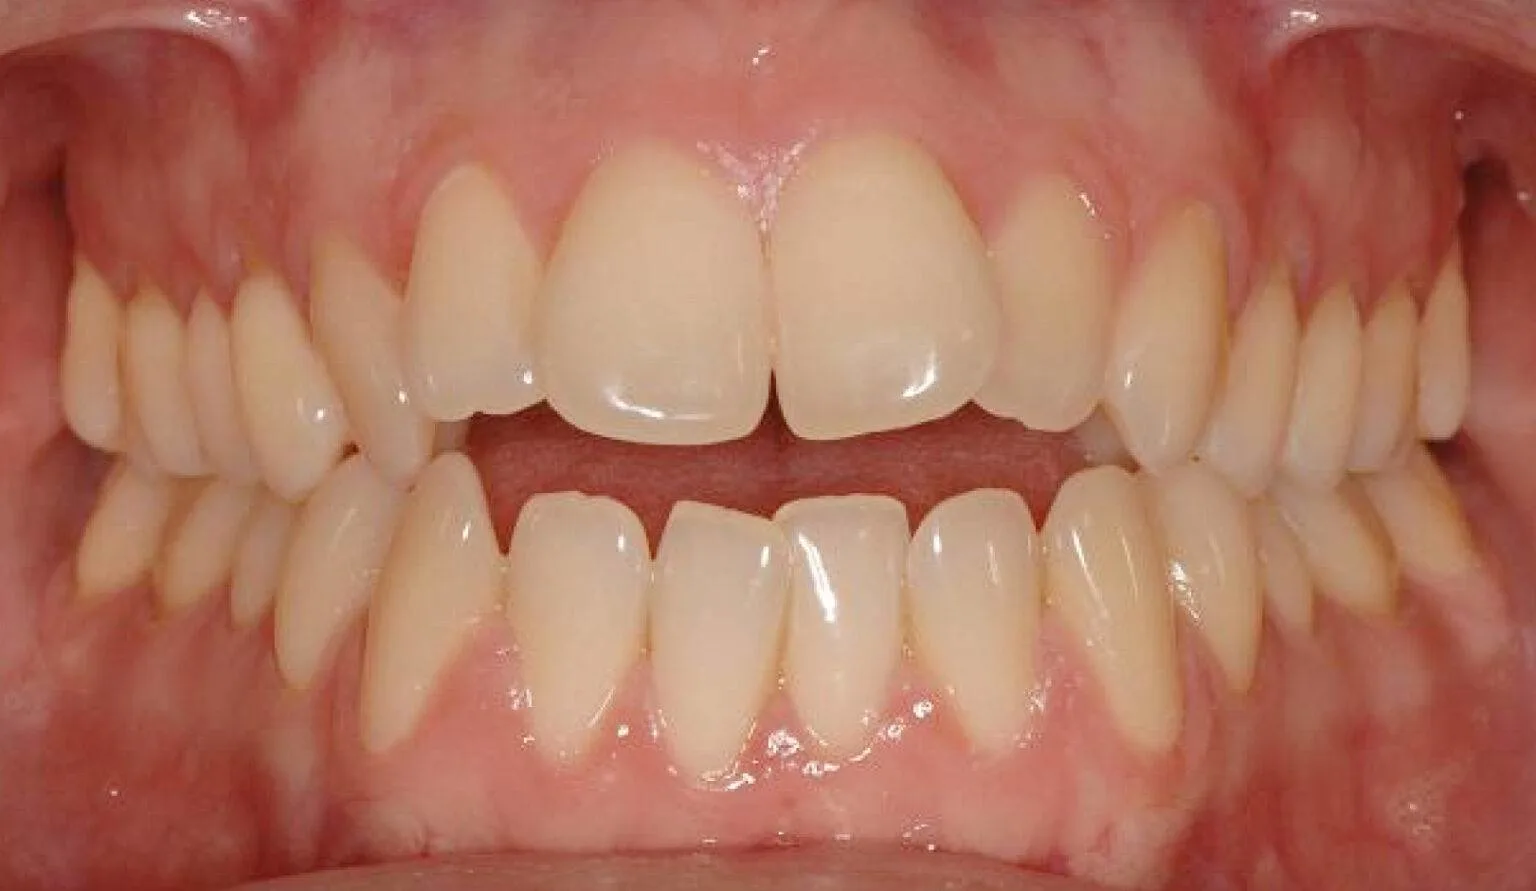

An open bite is a type of malocclusion (misalignment of teeth) where there is a gap or space between the upper and lower front teeth when the back teeth are closed together. This means that the front teeth do not make contact with each other when the mouth is closed, which can cause difficulty in biting and chewing food, speech problems, and jaw pain. Open bites can be caused by a variety of factors such as thumb sucking, tongue thrusting, genetic factors, or abnormal jaw growth.

Before & After Invisalign® Gallery